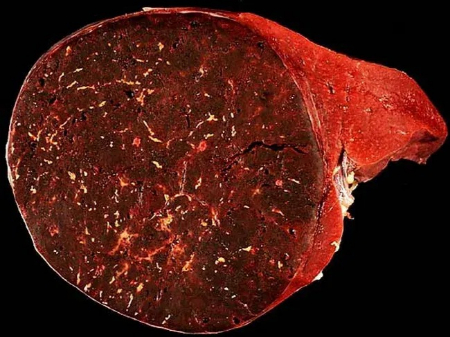

هامارتوما یک تومور غیرسرطانی (خوشخیم) است که از همان سلولهای موجود در بافت اطراف ساخته شده است، اما این سلولها و بافتها به صورت نامنظم و بینظم تومور میکنند. بیشتر هامارتوماها هیچ علامتی ایجاد نمیکنند و جدی نیستند. اگر هامارتوما مشکلی ایجاد کند، معمولاً با جراحی برطرف میشود.

هامارتوما (تلفظ: هَم-آر-تُو-ما) یک تومور شبهتوموری است که میتواند در هر جای بدن ظاهر شود. وقتی مردم کلمه «تومور» را میشنوند، اغلب به سرطان فکر میکنند، اما هامارتوماها سرطان نیستند. آنها فقط ترکیبی از همان سلولها و بافتهایی هستند که به طور طبیعی در آن ناحیه از بدن وجود دارند، اما به صورت نامنظم تومور کردهاند.

هامارتوماها بیشتر بیضرر هستند، اما اگر به اندازه کافی بزرگ شوند که به بافتهای مجاور آسیب برسانند، میتوانند مشکل ایجاد کنند. گاهی اوقات نیز نشانهای از بیماریهای ژنتیکی نادر مرتبط با افزایش خطر سرطان هستند.

هامارتوما هیچگاه به جاهای دیگر بدن پخش نمیشود